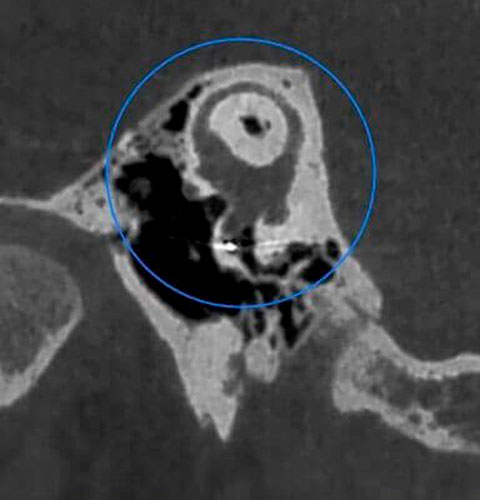

Veja exemplos de diagnósticos de imagem

Com apenas algumas etapas simples, o NNT pode processar os dados adquiridos durante a varredura para criar uma vasta gama de imagens, que fornecem informações detalhadas sobre a anatomia do paciente. Posteriormente, eles podem ser salvos em um relatório ou distribuídos com a versão Viewer do software. O NNT também oferece diferentes modos de aplicação voltados especificamente para implantologia, endodontia, periodontia, cirurgia maxilofacial e radiologia.